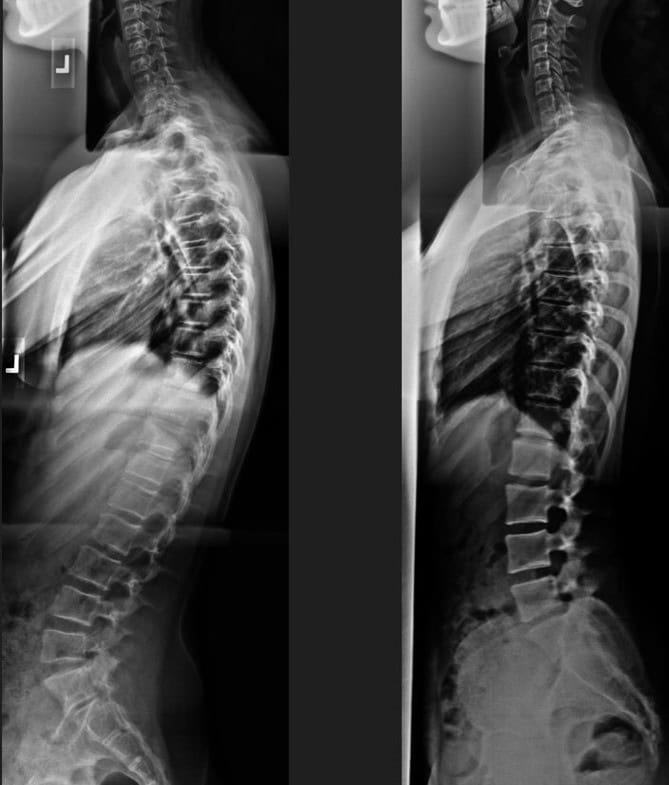

Pre & Post Scan